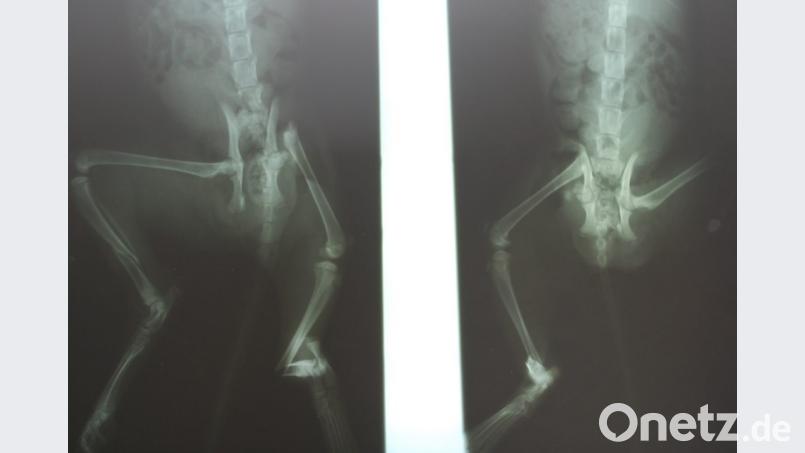

Das arme Tier wurde durch die Wucht regelrecht aus dem Motorraum geschleudert. Die Diagnose fiel erschütternd aus: Beckenbruch, Bauchbruch, Oberschenkelhals-Fraktur und beide Unterschenkel gebrochen. Das etwa vier Monate alte Katzenbaby muss unvorstellbare Schmerzen gehabt haben. "Es hat jämmerlich geschrien", erinnert sich der Veterinär.

Doch der weigerte sich: "Das ist kein Grund zum Einschläfern. So etwas kann man richten, egal, was es kostet." Daraufhin hat er das Tier angenommen "und nach und nach mit großem Aufwand auf eigene Kosten operiert". Zweimal drei Stunden dauerten Bauchbruch-, Becken und Hüft-OP sowie die Verplattung beider Unterschenkel mit medizinischem Stahl. Nach ein paar Tagen konnte das Kätzchen wieder laufen, mittlerweile ist es vollkommen genesen und erkundet schon neugierig und frech seine Umwelt.